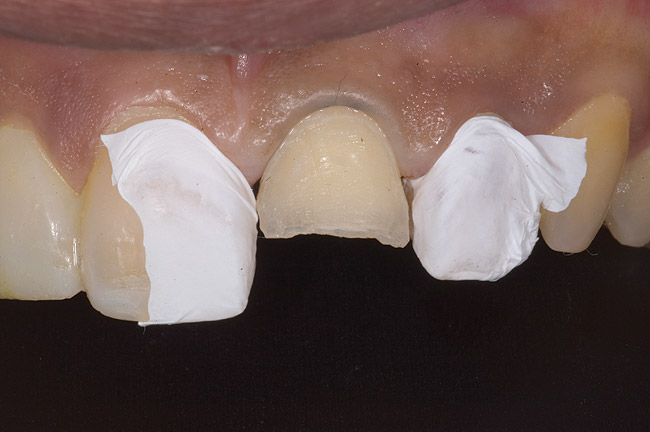

Figure 5  Thinning of the labial enamel and noncarious cervical lesions.

Figure 5

Figure 6  1:1 view demonstrating severe loss of tooth structure due to palatal erosion.

Figure 6

Figure 9: Tooth No. 9 minimally prepared for resin layering on the labial surface.

Figure 9

Figure 10  Tooth No. 9 with no preparation on the palatal surface to restore lost form with bonding resin.

Figure 10